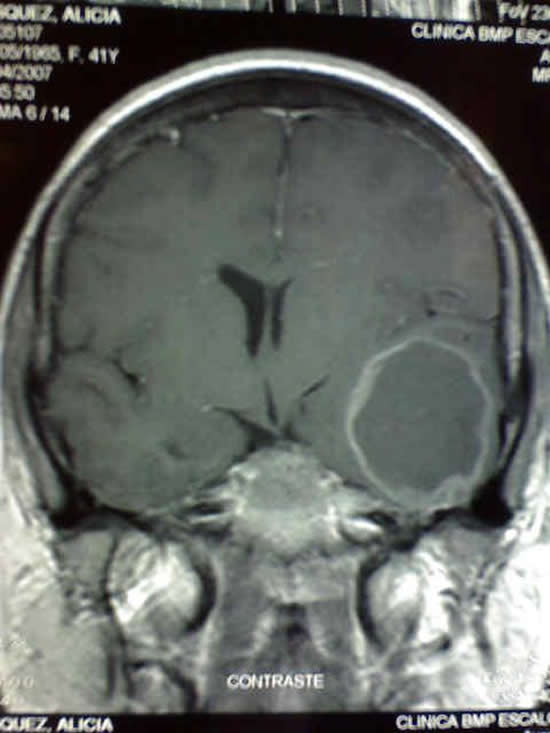

Enfermedades Infecciosas

Diversas infecciones pueden atacar el cerebro. En nuestro país la más frecuente es la neurocisticercosis cerebral, conocida como la enfermedad de parásito del cerdo. A pesar de su nombre, no se produce directamente por la ingesta de carne de cerdo, sino mas bien, por contaminación de los alimentos con heces de una persona que tiene teniasis intestinal. Los síntomas de este problema son dolor de cabeza, convulsiones, trastornos de la vista, deterioro del estado de conciencia, etc. Las complicaciones más temidas son la infestación masiva y la obstrucción del sistema ventricular, conocida como hidrocefalia. El tratamiento de la cisticercosis consiste en antiparasitarios, esteroides, anticonvulsivantes y en ocasiones procedimientos quirúrgicos.

Otros tipos de enfermedades infecciosas del cerebro que vemos en nuestro país son: tuberculosis cerebral, meningitis con encefalitis, toxoplasmosis, criptococosis, abscesos cerebrales, etc.. La figura de la izquierda muestra un absceso cerebral temporal izquierdo.